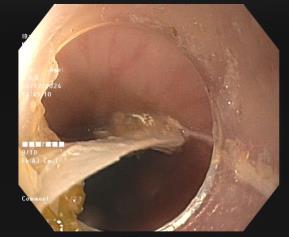

Trường hợp khác là bệnh nhân nữ 35 tuổi, trú tại phường Giếng Đáy, thành phố Hạ Long. Bệnh nhân bị hóc xương cá từ tối trước ngày vào viện, sau hóc cảm giác nuốt vướng, nuốt đau vùng cổ. Ekip nội soi Khoa Nội tiêu hóa đã tìm thấy dị vật xương cá lớn hình chiếc rìu, dài 03 cm, nhiều góc cạnh sắc nhọn mắc tại thực quản vị trí cách cung răng trên 17cm, bề mặt niêm mạc thực quản trầy xước nông, không chảy máu. Xương cá sau đó được gắp ra ngoài an toàn.

Dị vật xương cá mắc tại thực quản được gắp ra ngoài